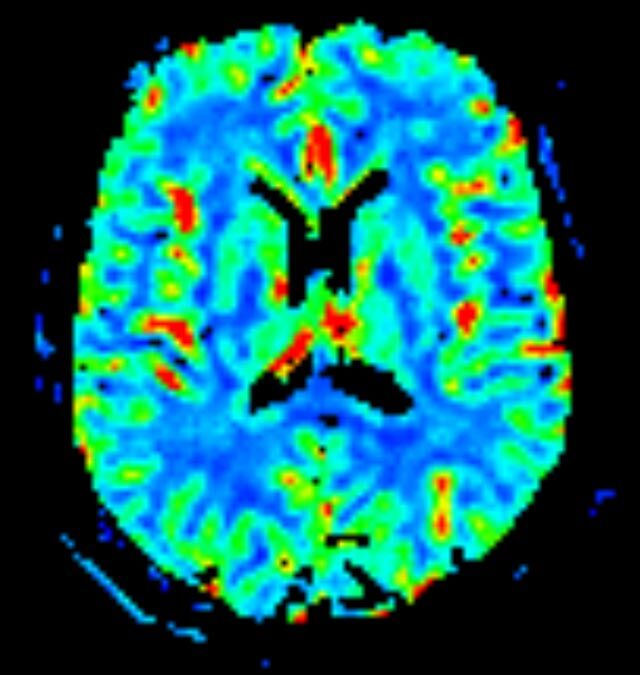

• Perfusionswichtung

Kopf/Hals

• akute Schlaganfalldiagnostik und chronische Durchblutungsstörungen